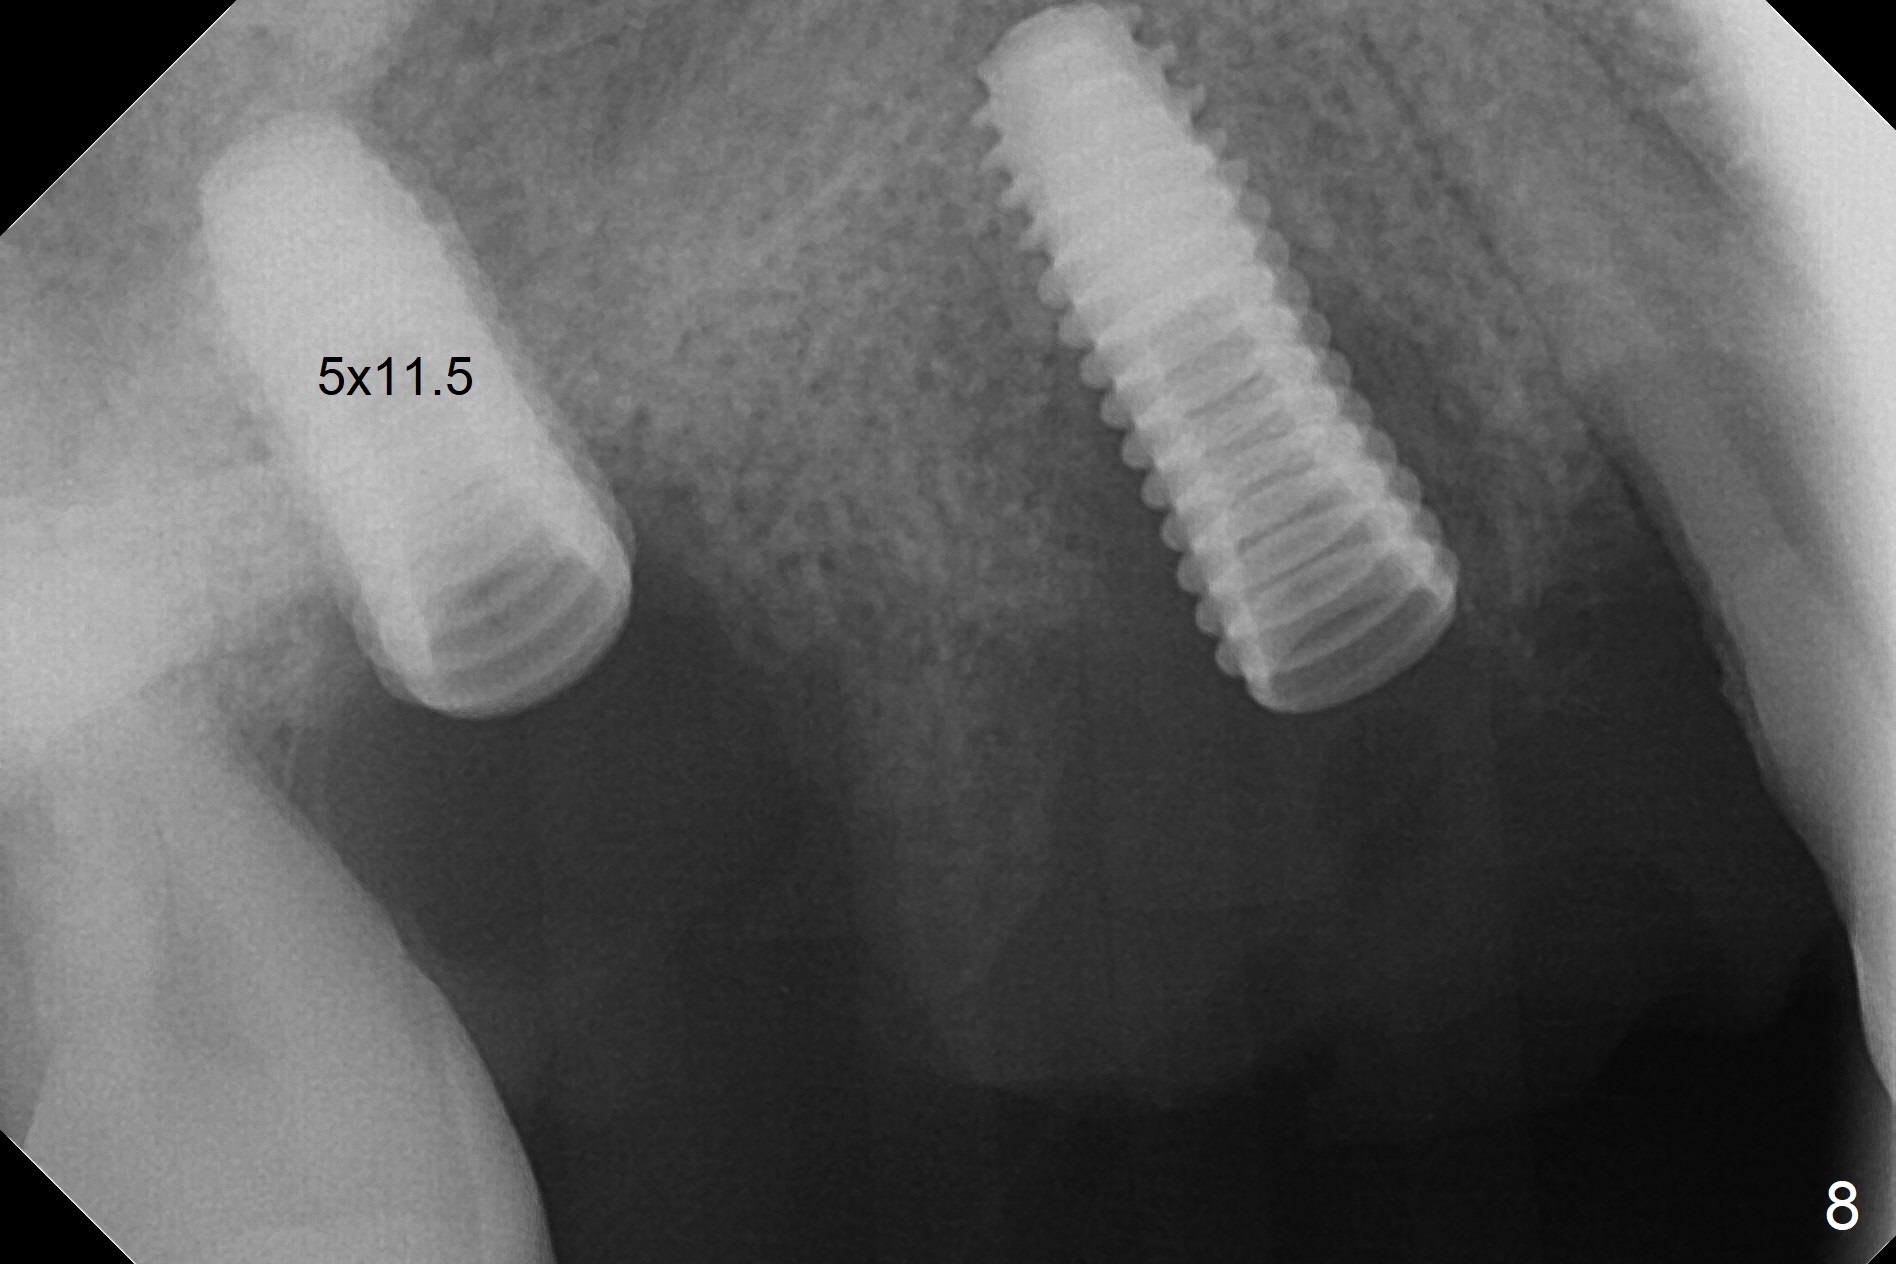

The 36-year-old man (ex-smoker, quit for 4-5 years) insists upon #3 and 5 extraction first for implants, in spite of more severe infection at #7, 14,19,30 (Fig.1-4). The gingiva around #23-26 implants is healthy 3 weeks postop (Fig.5). The initial depths at #3 and 5 are 8.5 mm (bone-level) and 18 mmm (gingiva-level (13 mm (implant length) + 5 mm cuff), respectively. When a drill penetrates the sinus floor, confirm the depth. After use of 3.8 mm drill, 4.5 mm tap drill is inserted at #3 without stability, while a 4.5x13 mm implant is placed at #5 with primary stability (Fig.6,7). Then a 5x11.5 mm is placed at #3 subcrestal proximally after sinus lift with Vanilla graft (without sinus membrane perforation; Fig.8). The implant at #5 is seated ~1 mm deeper (subcrestal mesially (^^); supracrestal distally (^)); allograft is placed around the implants prior to insertion of 6.5x7(5) and 5.5x4(5) mm abutments; last more allograft is added (Fig.9 *, 10). The implants seem to have been osteointegrated 4.5 months postop (Fig.11,12). The gingiva is healthy around the implants without bone loss 3 months post cementation (Fig.13,14).